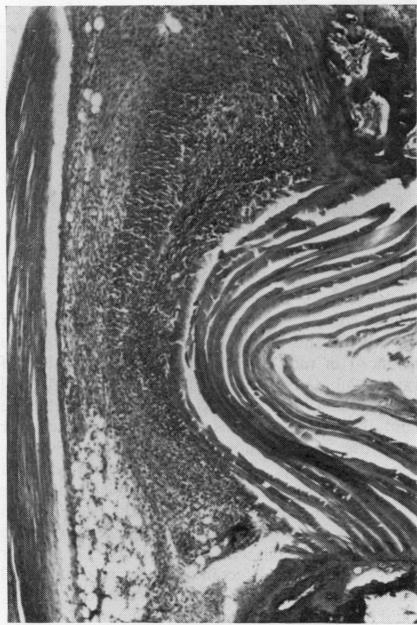

Workshop IV. Aetiopathogenetic factors in Reiter's syndrome. Adjuvant disease: pathology and immune reactivity.

Ann Rheum Dis. 1979;38 Suppl 1(Suppl 1):suppl 102-10. doi: 10.1136/ard.38.suppl_1.102.